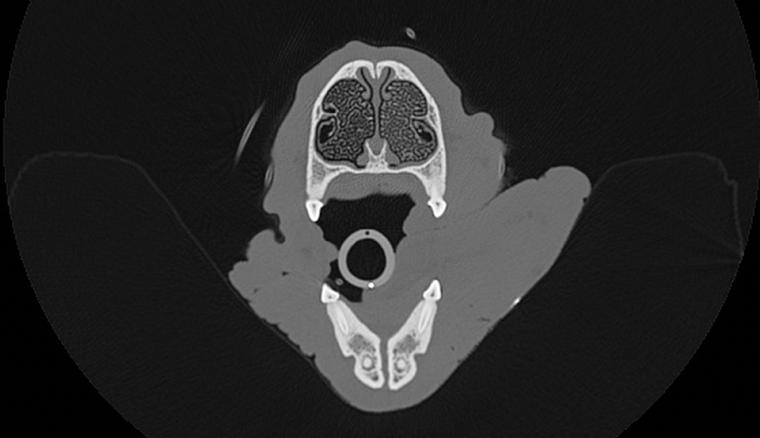

Lundi 5 Fevrier 2018 Animaux de compagniePhoto n° 1 Coupe transverse des cavités nasales en partie rostrale. Les cornets nasaux sont bien visibles. La muqueuse nasale est plus épaisse du côté gauche comparativement au côté droit. Ceci est normal et correspond au cycle nasal.